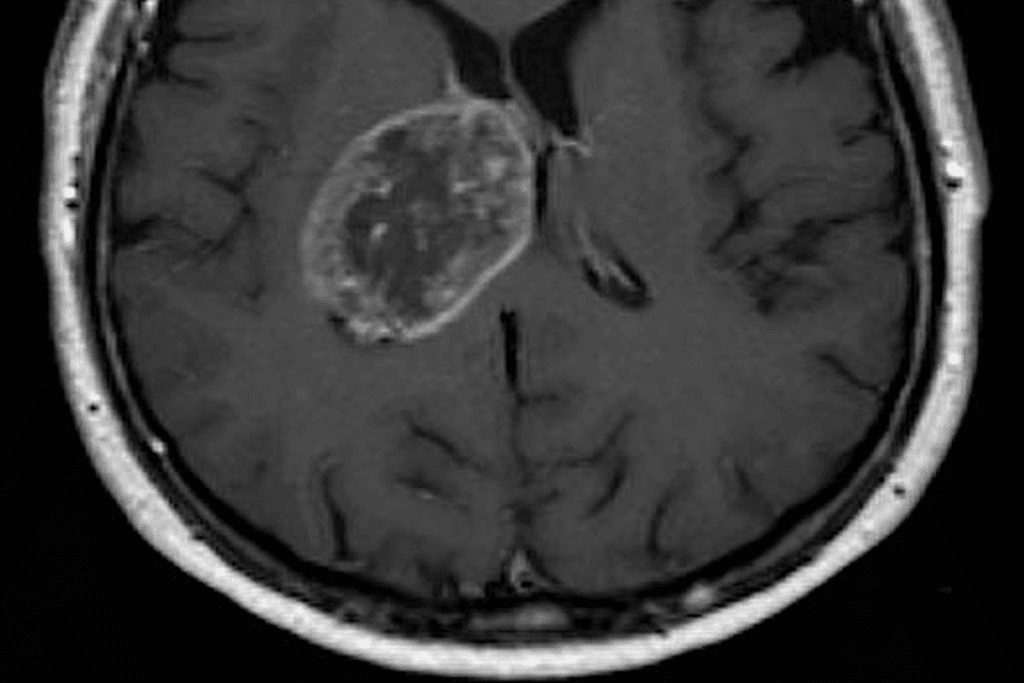

Imaging Tests

Imaging tests are very important for diagnosing brain tumors in kids. The main tests are:

- Magnetic Resonance Imaging (MRI)

- Computed Tomography (CT) scans

- Positron Emission Tomography (PET) scans

These tests help doctors see the tumor, its size, and where it is. They also check how it affects the brain around it.

Biopsy and Other Procedures

At times, a biopsy is needed to confirm the diagnosis. A biopsy takes a tumor sample for microscopic examination. Other tests, like a lumbar puncture (LP) or spinal tap, might also be done. These check for cancer cells in the cerebrospinal fluid.